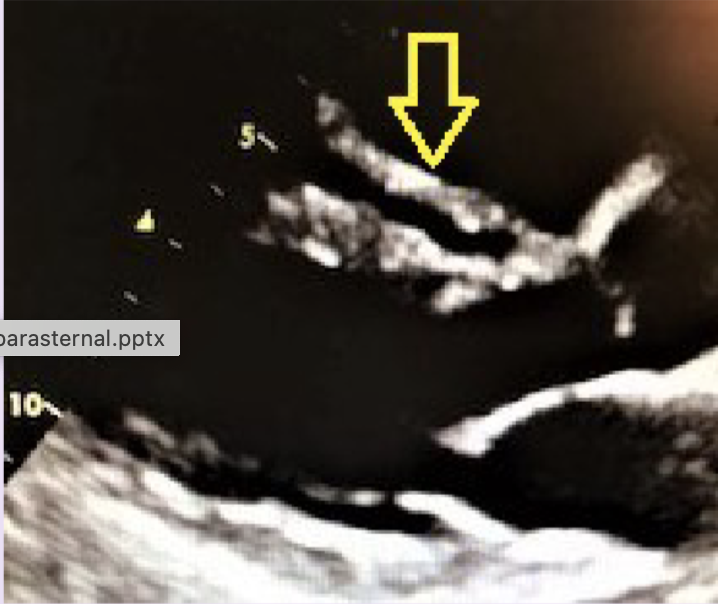

Q

What is the arrow pointing to?

A

AMVL continuity